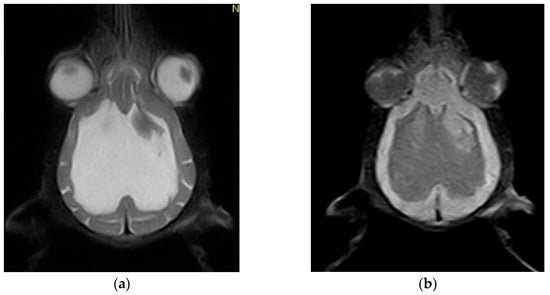

2. Case Description

- Raposo, M.; Añor, S.; Verdés, J.; Soler, V.; Martorell, J. Diagnosis and Treatment of Congenital Hydrocephalus in a Red Fox (Vulpes vulpes) with Seizures. Vet. Rec. Case Rep. 2022, 10, e310. [Google Scholar] [CrossRef]